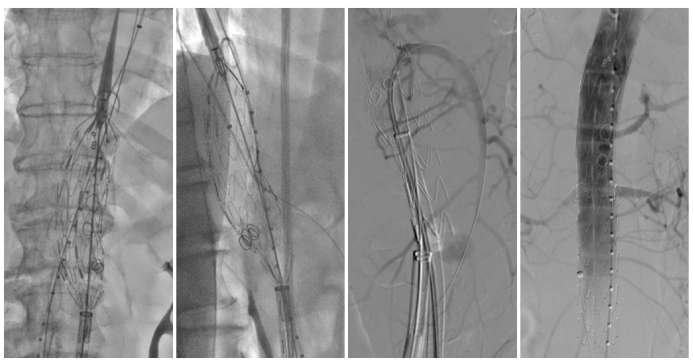

实战案例与应急处理

理论源于实践,中山医院团队展示了多例成功病例,涵盖假性动脉瘤、腹主动脉瘤及胸腹主动脉夹层,术后随访效果满意,充分验证了该技术的可靠性。

★ Case1:男,60岁,假性动脉瘤

★ Case2:男,69岁,腹主动脉瘤。全程束径。

★ Case3:术中束径丢失,如何处理补救?男,72岁,胸腹主动脉瘤。

在一例胸腹主动脉瘤手术中,发生了罕见的“束径丢失”(束径导丝意外脱出),导致支架提前贴壁。面对危机,团队并未慌乱,而是迅速采取补救措施:

立即建立生命线: 从上肢紧急穿刺置入6F鞘,优先超选并保护SMA。

逆向思维,化险为夷: 在SMA这条“生命线”保障下,从容地从股动脉重新尝试超选其他分支,最终成功完成手术,避免了开腹手术。